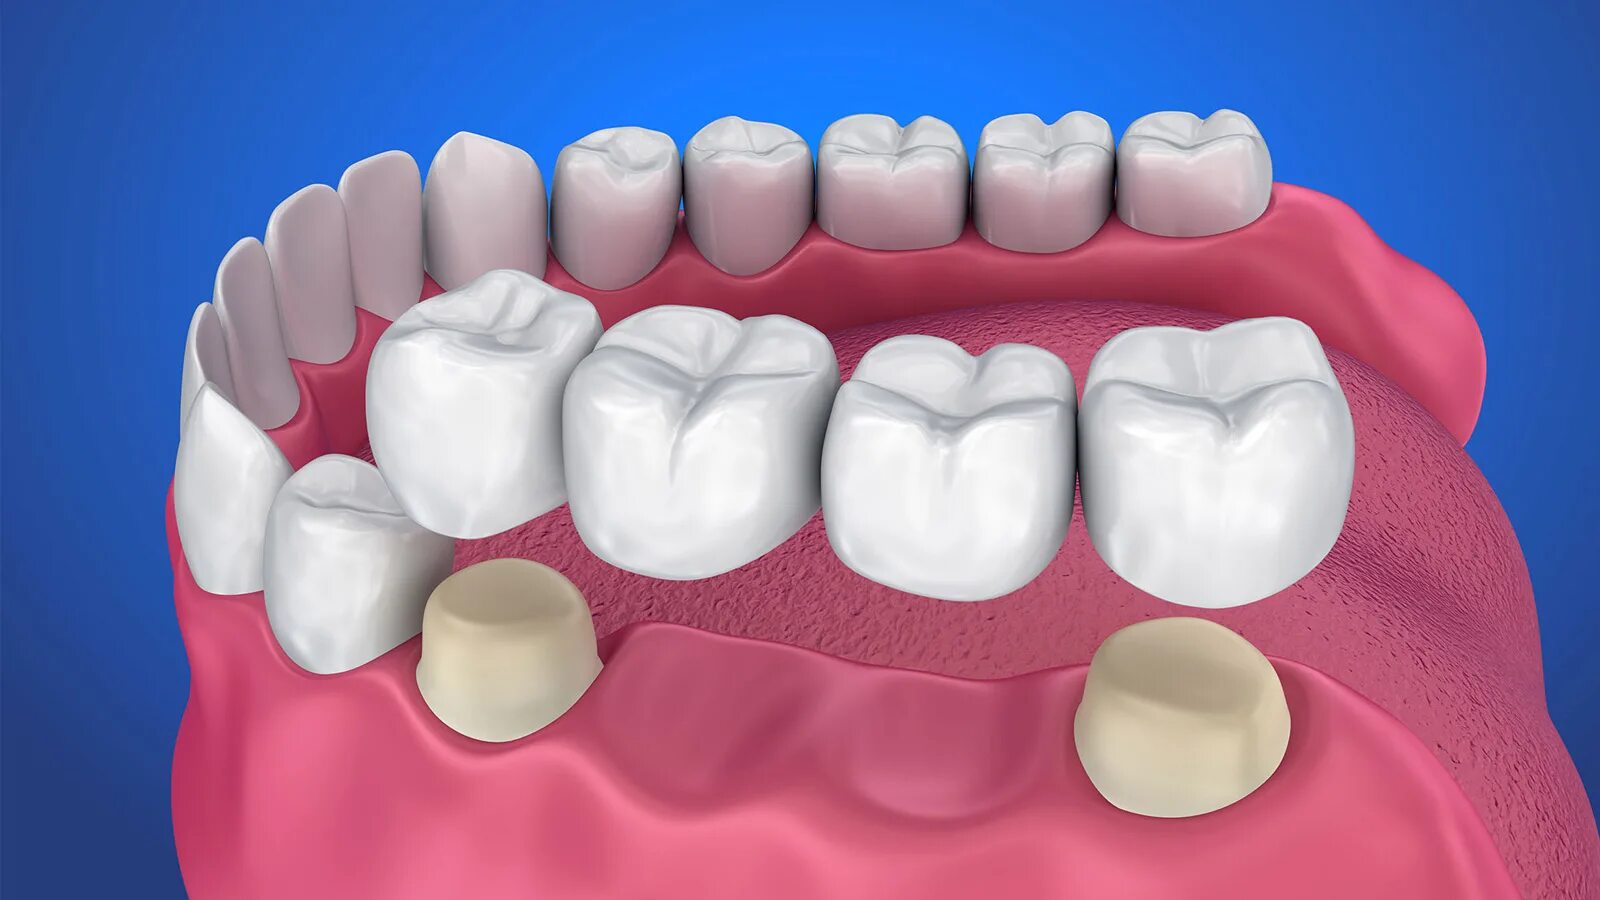

Поставить 4 зуба